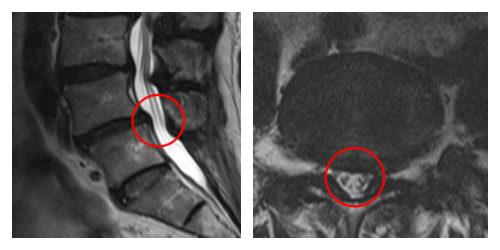

┃検査・診断

赤い枠で示されている部分(L4/5 )にヘルニアが認められました。